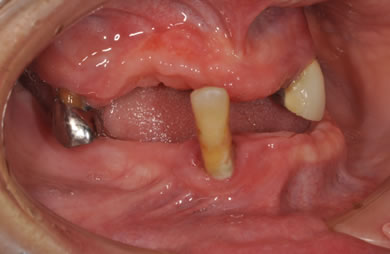

インプラントの症例写真 IMPLANT

骨再生スピードインプラント治療+AGC連結セラミック治療

| 性別/年齢 | 女性 / 57歳 | ||||||||||||||||||||||||||||||||

| 主訴 | 全体的に歯が無いので相談したい。 | ||||||||||||||||||||||||||||||||

| 治療内容 | インプラント12本(サイナスリフト+GBR+抜歯即日スピードインプラント+遊離歯肉移植)、AGCハイブリッドセラミック連結ブリッジ2装置(上顎・下顎)、テンポラリーインプラント2本 | ||||||||||||||||||||||||||||||||